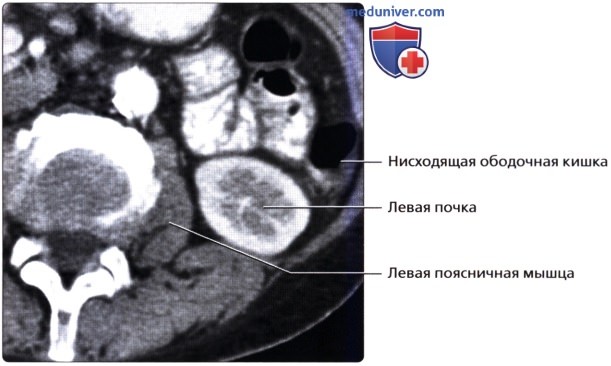

а) Анатомия почек:

2. Топографическая анатомия почки:

• Лежат в забрюшинном пространстве, окружены почечной фасцией (фасция Героты)

• У взрослого каждая почка около 9-14 см в длину и 5 см в ширину

• Обе почки лежат «на» квадратных мышцах поясницы, латеральнее поясничных мышц

3. Внутренняя структура:

• Корковое вещество почки: периферическая часть, содержит почечные (клубочки, сосуды), проксимальные части собирательных трубочек и петли Генле

• Мозговое вещество почки: внутренняя часть, содержит почечные пирамиды, дистальные части собирательных трубочек и петли Генле

б) Лучевая анатомия почки:

1. Обзор:

• Забрюшинные структуры бобовидной формы с четким контуром, смещающиеся при дыхании